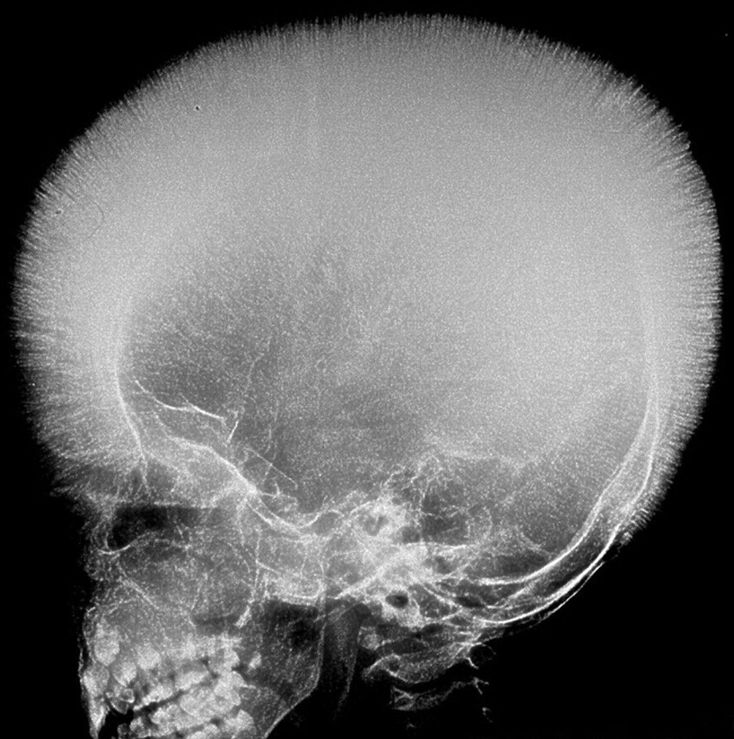

The hair on end sign refers to a radiographic appearance of the diploic space of the skull vault which results from a thickening of trabeculae as the diploic space expands. These trabeculae are perpendicular in orientation, interspersed by radiolucent marrow hyperplasia along the skull vault. It is classically described with plain skull radiographs although can also be appreciated on CT or MRI . Causes include: thalassaemia major sickle cell disease hereditary spherocytosis iron deficiency anaemia......Mnemonic HI NEST ..... hereditary spherocytosis iron deficiency anaemia neuroblastoma enzyme deficiency, e.g. G-6-PD deficiency causing haemolytic anaemia ,sickle cell disease ,thalassemia major

Hair on end appearance....seen in Thalassemia and sickle cell anemia

Hereditary spherocytosis, Iron deficiency anaemia , Neuroblastoma , Enzyme deficiency(G-6-PD deficiency causing haemolytic anaemia), Sickle cell disease thalassemia major